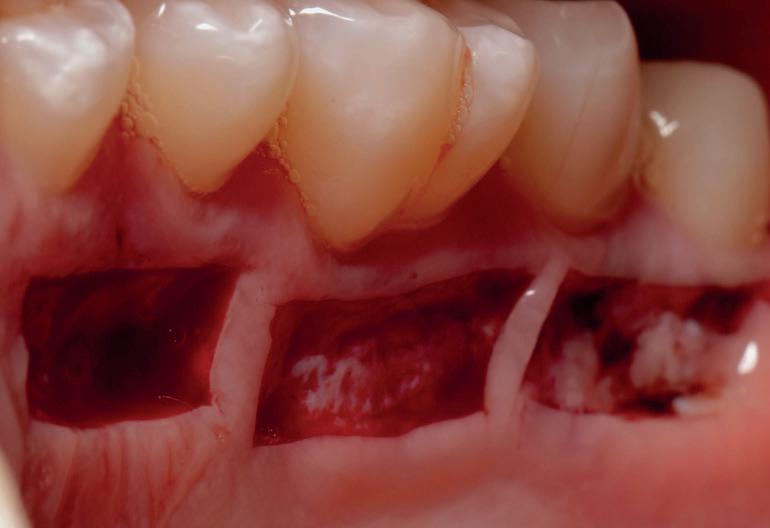

EthOss® is a 100% synthetic bone graft material for dental implant surgery. With no risk of cross-contamination, EthOss® works with the body’s healing process by creating a calciumrich environment and is completely absorbed.